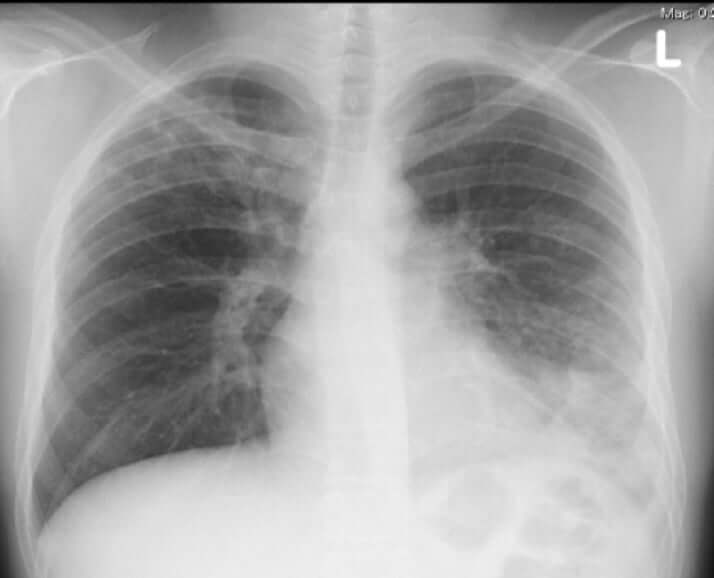

3枚目/4枚中

社会2025年11月04日

マイコプラズマに感染した患者の体内